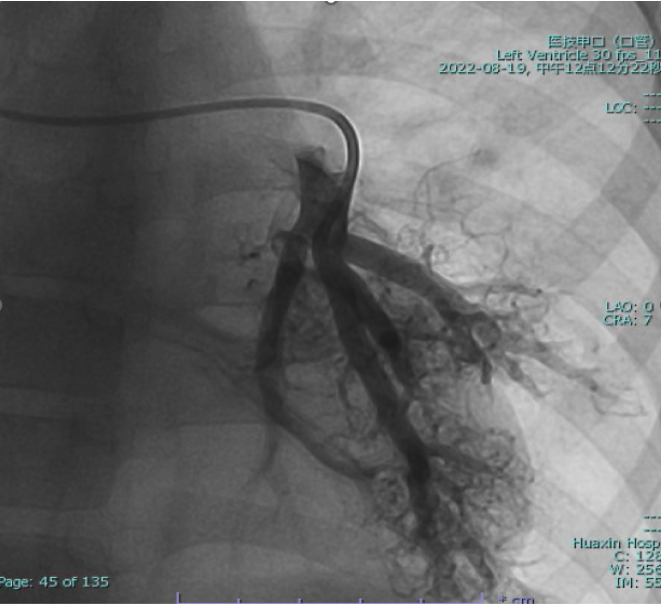

Cardiac catheterization confirmed absence of antegrade pulmonary flow with well-developed bilateral pulmonary arteries. Distal pulmonary arteries and pulmonary venous branches were markedly dilated, some showing a granular or ¡°string-of-beads¡± appearance. Pulmonary circulation time was shortened, indicating significant right-to-left intrapulmonary shunting consistent with diffuse PAVMs. Pulmonary artery pressure was 17/9/13 mmHg.

The operation was performed via a median sternotomy. Intraoperative exploration revealed that the ventricular septal defect was located in the inflow tract, distant from the aortic valve, making intracardiac tunnel construction infeasible; therefore, biventricular repair was not feasible. Under general anesthesia with hypothermic cardiopulmonary bypass, a total cavopulmonary connection (TCPC) was performed. The inferior vena cava was transected, and an 18-mm Gore-Tex conduit was anastomosed end-to-side to the right pulmonary artery, establishing a complete cavopulmonary circuit. Immediate postoperative oxygen saturation was approximately 75%. The total operative time was 6 hours and 14 minutes, with an aortic cross-clamp time of 50 minutes. The patient remained in the intensive care unit for 8 days and was discharged on postoperative day 19 after an uneventful recovery and stable hemodynamics. During a 2-year follow-up, peripheral oxygen saturation gradually increased and stabilized at 97–100%, with markedly improved exercise tolerance, resolution of digital clubbing, and normal skin color. Repeat cardiac catheterization confirmed unobstructed conduit flow and well-developed pulmonary vasculature. The previously extensive bilateral pulmonary arteriovenous malformations had completely resolved, pulmonary circulation time normalized, and pulmonary artery pressures measured 13/11/12 mmHg.